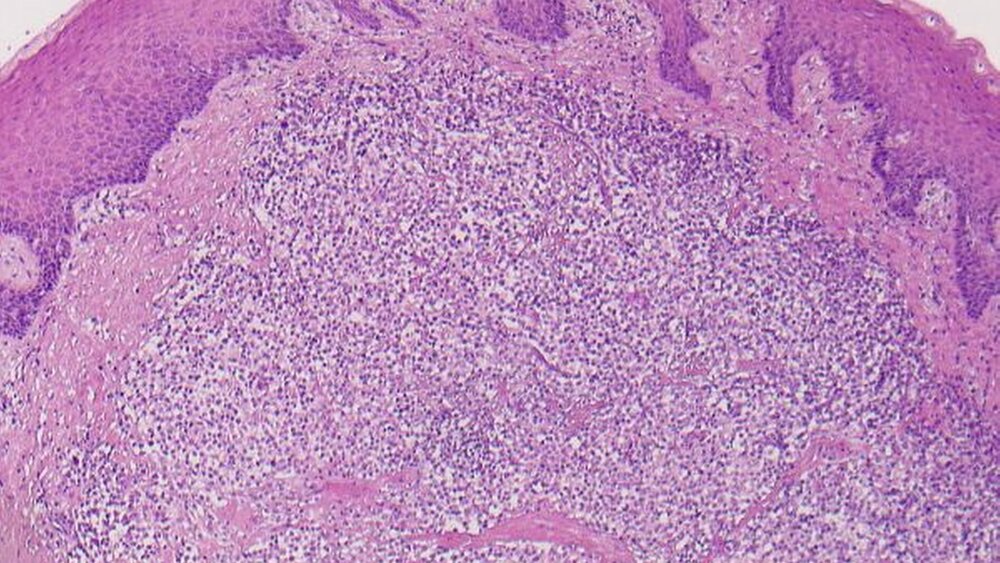

Die histopathologische Aufarbeitung des Resektats ergab eine floride chronisch unspezifische Gingivitis mit reaktiver Schleimhaut ohne Anhalt für Malignität.